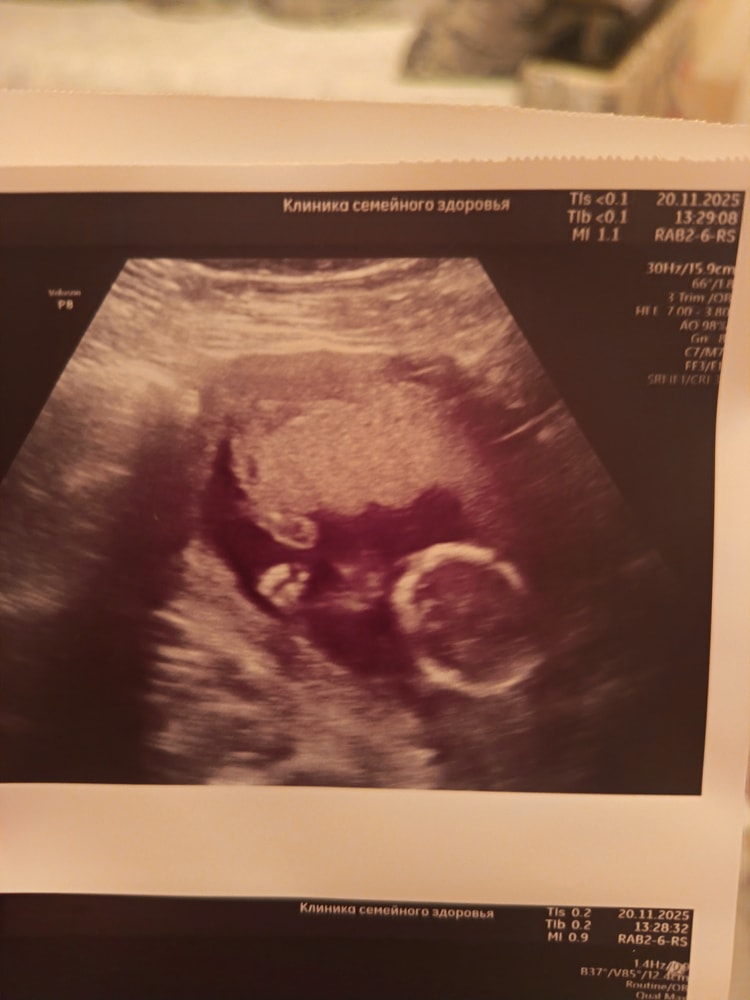

20.11 была на УЗИ, врач всё посмотрела, сказала отлично, малыш растёт. Пол врач увидела, но как мы с мужем и решили, будем делать гендер пати когда он приедет с вахты в середине декабря, эх терпения мне🤭😁уже не терпится узнать кто же там в животике живёт 😍 на УЗИ малыш как врач сказала с характером, даже не получилось сделать красивые снимки, лежит не удобно, но как по мне, эти даже ещё лучше🥰💗 сначала спал, мы его пока делали УЗИ разбудили, малыш стал кулаки показывать, попу, а в конце вообще спиной развернулся😁🤭 на секунду даже показалось что мальчишка😊 по весу написали 118 +/- грамм счастья😍 девушки, у кого примерно такой же срок, как у вас дела, как самочувствие? 😊